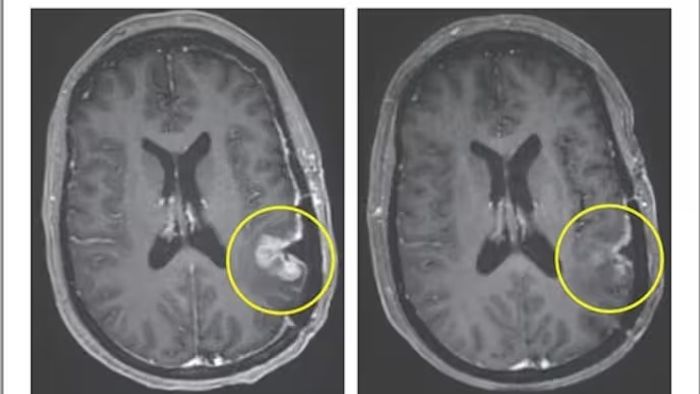

এই ট্রায়ালে ৩ জন রোগী অংশ নেন। তাদের বয়স ছিল ৫৭ থেকে ৭৪ বছরের মধ্যে। তারা আগে রেডিয়েশন ও কেমোথেরাপি নিয়েছিলেন। ফলাফলে দেখা যায়, একজন রোগীর টিউমার দ্রুত কমে, কিন্তু তা স্থায়ী হয়নি। আর একজনের ক্ষেত্রে ৬০ শতাংশের বেশি টিউমার কমে এবং তা ছয় মাসের বেশি সময় স্থায়ী হয়। তৃতীয় রোগীর ক্ষেত্রে মাত্র ৫ দিনের মধ্যে প্রায় সম্পূর্ণ টিউমার সঙ্কুচিত হয়ে যায়।